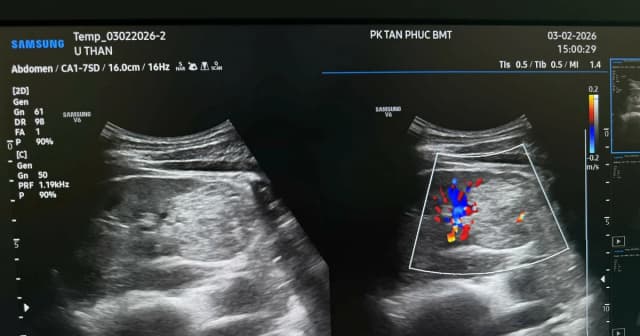

GD&TĐ - Một người đàn ông ở Lâm Đồng, đến khám định kỳ tại Phòng khám đa khoa Tân Phúc Buôn Ma Thuột (Đắk Lắk) thì phát hiện bị ung thư thận.